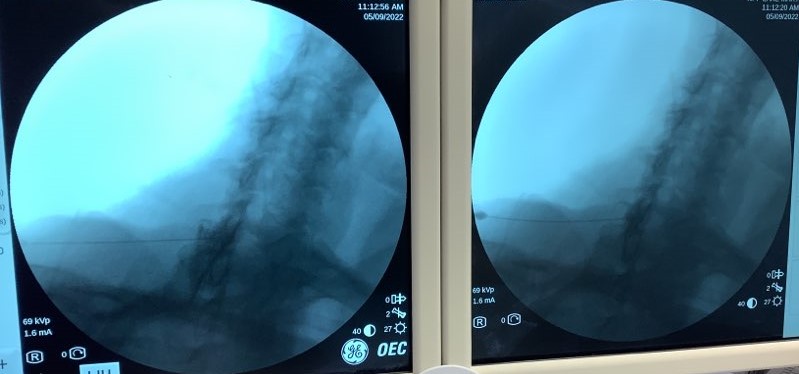

CLO @ 50 degrees with 25G Quincke tip - does this seem epidural?

Looks posterior to me

Posterior. Collimated views would tield better pics and more accuracy.

looks mostly posterior but some epidural spread by C7. probably your toes were through the door

agreed, it seems posterior.

Posterior. When in doubt grab a lateral. It’s not much use for getting the needle in but once you’ve injected the contrast you can usually see a nice clear posterior epidural stripe even if the CLO is unclear. Agree with comments Re: collimation as well.

Posterior, that line going from anterior upper lamina to posterior lower lamina is typical spread when your just posterior and think you get a false loss. Put stylet back in to get good view of needle tip, columinate in, check AP to make sure your still under contra lateral lamina. I don’t typically do a lateral in cervical spine for ESI because the contra lateral is always a superior view. Advance another 1mm and your probably epidural.